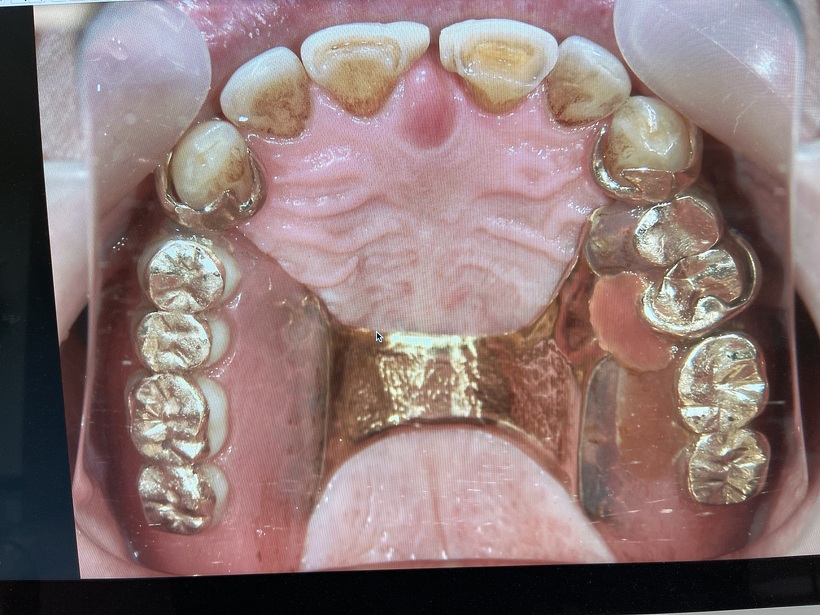

上顎の義歯と残存歯 一部修理

当時当院は保険診療をしていましたが患者さんに自費の義歯の作成を許可して頂きました。初診より1年半後新しい上下の部分義歯が完成しました。最高の金属(白金加金)を使用したため上下で70万円になりました。支払い時患者さんは「高いな~!」と思われたそうです。義歯装着より25年余りが過ぎ多少の修理はあったもののそのままの義歯を快適に使用出来ています。最近の感想は「こんなにも安い買い物は他になかった‼」です。